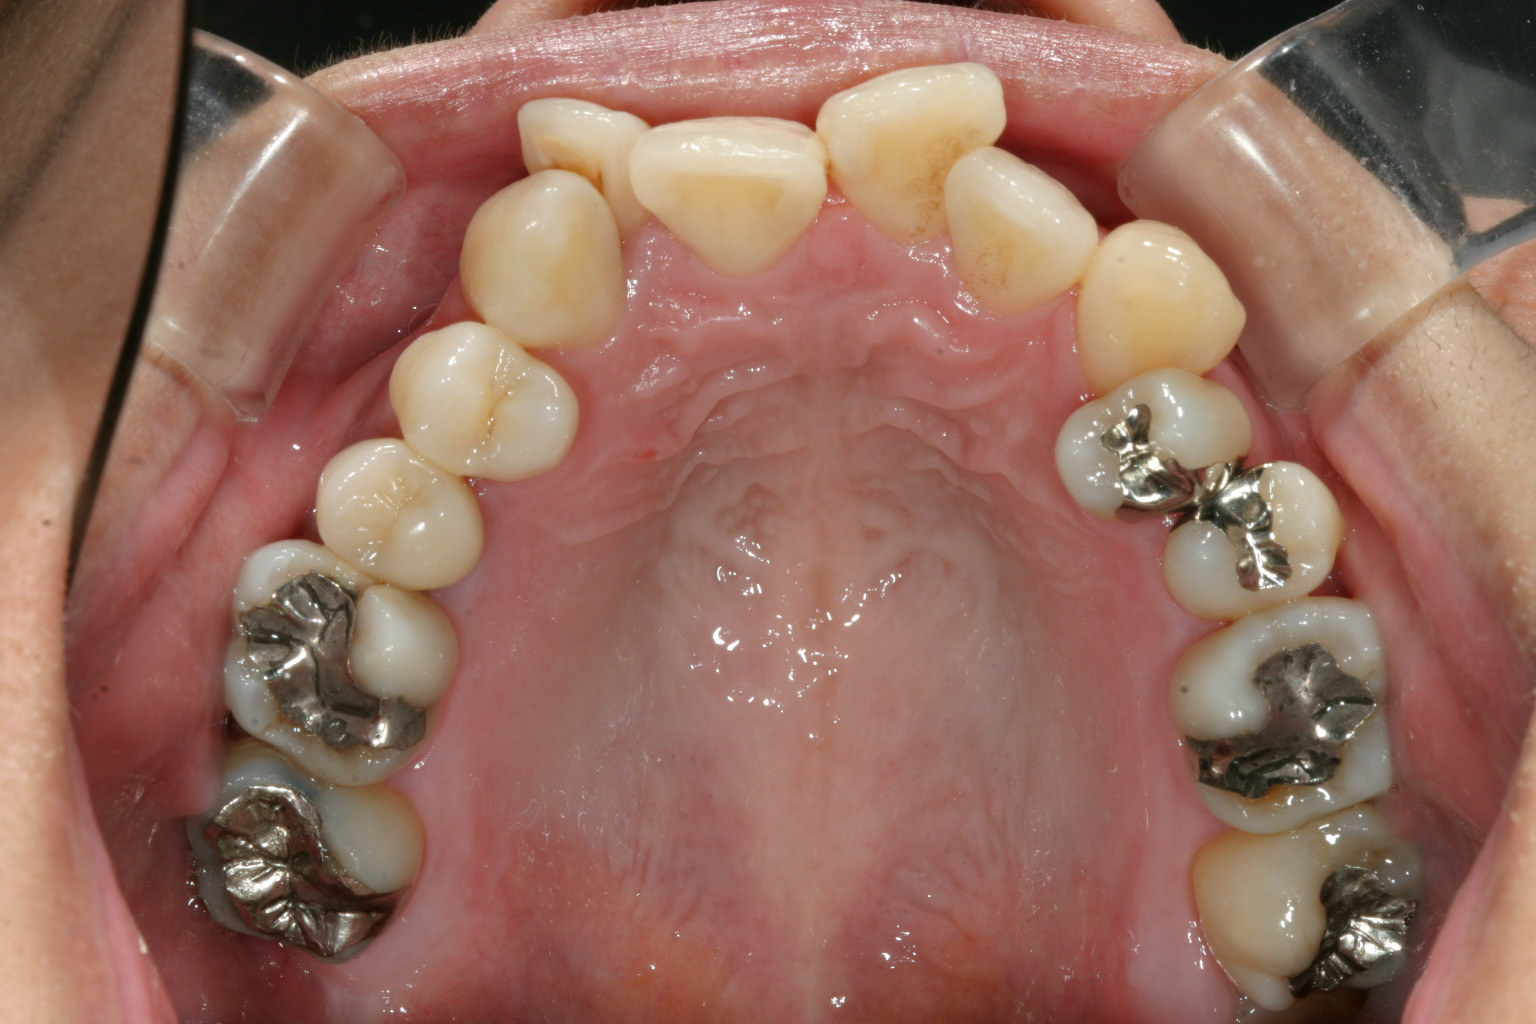

かなり酷くガタガタになってますね~ 数本の回転してる歯が在りますね~

下顎も歯があちこち回転してますでしょ~ これはかなり大変です。